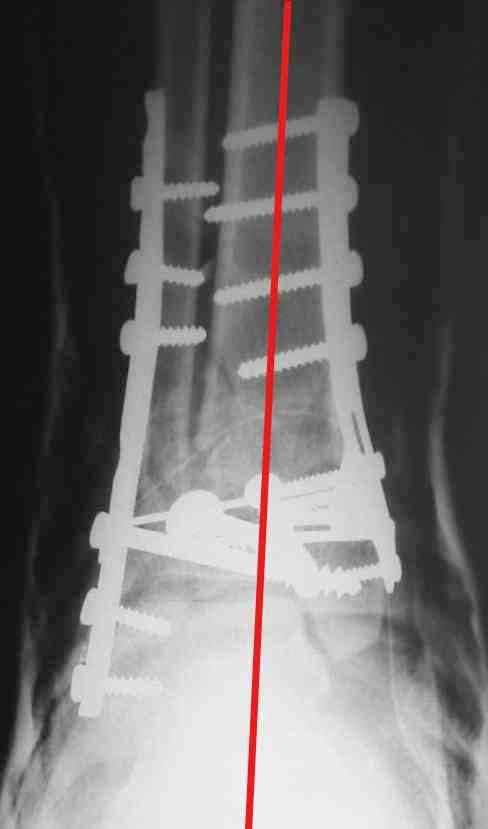

Re: Perelom N/3 kostei goleny

На представленном снимке видно, что эпифиз смещен латерально.

Сейчас с этим ничего не сделать, похоже.